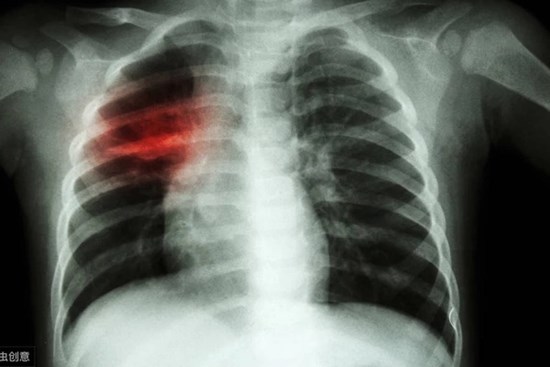

Phát hiện ung thư phổi sau 1 tháng ho vặt, tức ngực, dấu hiệu chỉ ra bệnh hiểm

Trước khi vào viện 1 tháng, ông V.V.V ở Quảng Ninh bị tức ngực và thỉnh thoảng húng hắng ho. Ông chỉ nghĩ đó là bệnh lý người già.